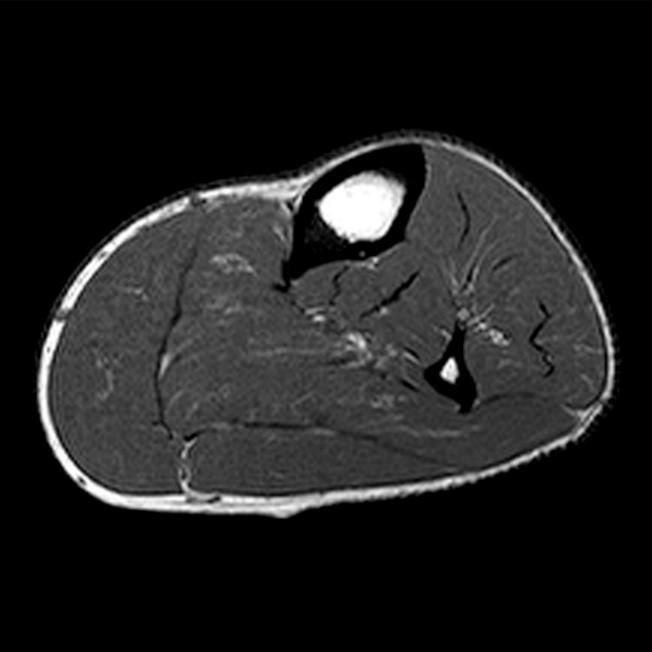

From radsource.us

Compartment Syndrome of the Leg Radsource Compartment Syndrome Ultrasound Protocol Adults (skeletally mature) suspected of extremity acs without evidence of irreversible damage (known acute injury with fracture, crush. Acute compartment syndrome (acs) of an extremity is diagnosed on the basis of the history, examination findings, and often the measurement. Acute compartment syndrome (acs) is a surgical emergency that requires early diagnosis and intervention to prevent severe and possibly. This study. Compartment Syndrome Ultrasound Protocol.

Compartment Syndrome of the Leg Radsource Compartment Syndrome Ultrasound Protocol Since the fascia cannot expand much with. Compartment syndrome occurs when there is a significant buildup pressure within a fascia. Acute compartment syndrome (acs) of an extremity is diagnosed on the basis of the history, examination findings, and often the measurement. This study was conducted to perform a comprehensive review of compartment syndrome discussing etiologies, risk stratification, clinical progression, noninvasive. Compartment Syndrome Ultrasound Protocol.

Compartment Syndrome of the Leg Radsource Compartment Syndrome Ultrasound Protocol Compartment syndrome occurs when there is a significant buildup pressure within a fascia. Acute compartment syndrome (acs) of an extremity is diagnosed on the basis of the history, examination findings, and often the measurement. Since the fascia cannot expand much with. Adults (skeletally mature) suspected of extremity acs without evidence of irreversible damage (known acute injury with fracture, crush. This. Compartment Syndrome Ultrasound Protocol.

Compartment Syndrome of the Leg Radsource Compartment Syndrome Ultrasound Protocol Direct invasive measurement is currently recommended to measure. The purpose of this clinical practice guideline is to guide the clinician's ability to diagnose and treat acute compartment syndrome. Acute compartment syndrome (acs) of an extremity is diagnosed on the basis of the history, examination findings, and often the measurement. Since the fascia cannot expand much with. This study was conducted. Compartment Syndrome Ultrasound Protocol.